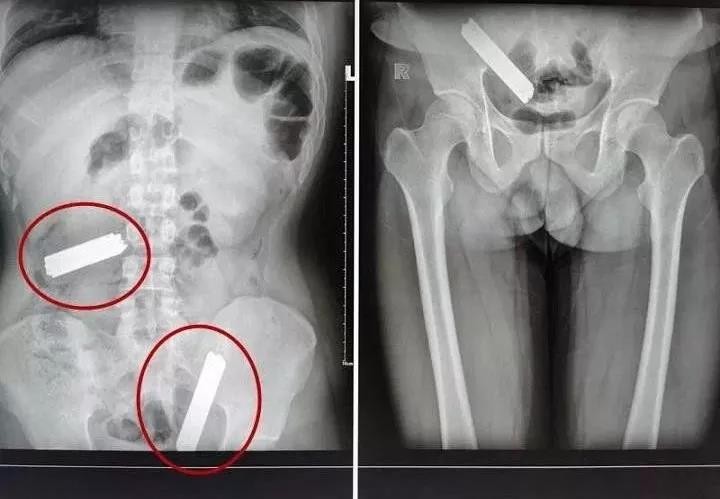

▲揭陽一名病人體內找到70支刀片。(圖/翻攝自《揭陽民生熱線》微信公眾號)

病人入院後,醫生又為病人作了進一步檢查,結果仍然顯示腹部有異物,但病人卻沒有明顯的症狀。醫生哪裡不舒服,病人都說沒有,其腹部也比較軟,沒有壓痛感,但從X光照中可以看到其體內有兩塊6、7公分的異物。

醫生在當天中午為病人進行手術,本來以為只是取兩塊金屬片,但術中探查時醫生震驚了,病人腹部藏的是美工刀片,而且越查越多,整個手術過程就像進行一場驚險的「魔術」表演。

醫生表示,光是在迴腸回盲瓣1.5米的地方探查到第一塊異物殘留處,做了小切口取出來,第一處大概就有32塊刀片,最終醫生總共從病人腹中取出的刀片多達70塊,所幸沒有再傳出有其他異物遺留體內。